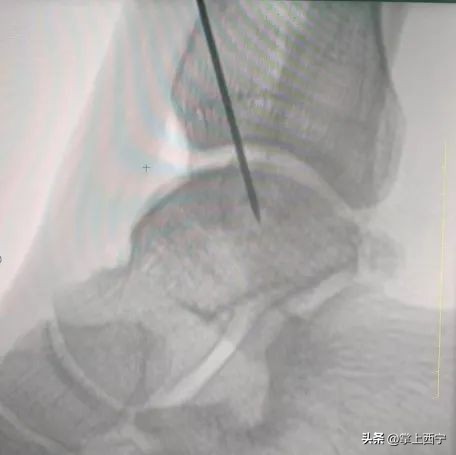

↑ 术中显露、定位病灶

术中全生炳医师和于贵鑫医师熟练地进行取距骨前方非负重区正常带软骨帽骨柱,取内踝部分松质骨,将松质骨及骨柱植入坏死区,透视见病灶清除彻底,关节面平整满意,手术过程非常顺利。